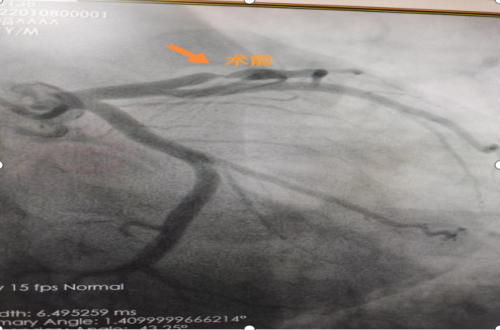

微创介入治疗,打通心脏血管“生命线”!

近日,我院微创介入中心手术室外,刚刚结束手术的心血管内科副主任龙泉杉疲倦的脸上挂着笑容,对守候在外的患者家属说:“手术很...